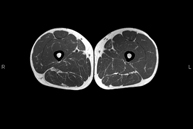

Exploració ideal per estudiar les lesions en músculs isquiotibials i quàdriceps, sovint lesionats en esportistes. També permet una bona valoració de tendons i de nervis perifèrics. La durada aproximada és de 20 minuts. No utilitza radiació ionitzan. - RM de Genoll